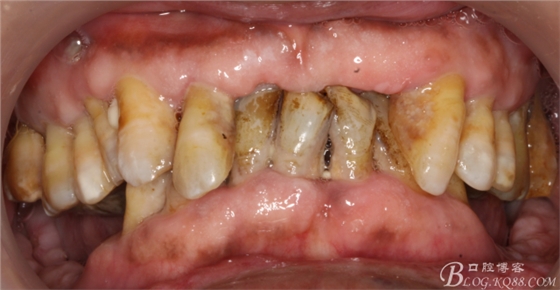

這個(gè)病例,是我的患者經(jīng)過(guò)治療之后感到很滿意,帶著她的父親來(lái)到我們塘沽口腔醫(yī)院來(lái)就診。

病人上前牙缺失,下頜前牙伸長(zhǎng)已經(jīng)咬到上頜牙槽脊,看x線片

牙槽骨嚴(yán)重吸收,全口牙還剩下21顆牙,但是 在1度松動(dòng)的牙齒只有12顆牙,其它牙都在2度到3度松動(dòng)之間

上頜--15、13、23、24、25

下頜--44、43、42、41、32、33、34